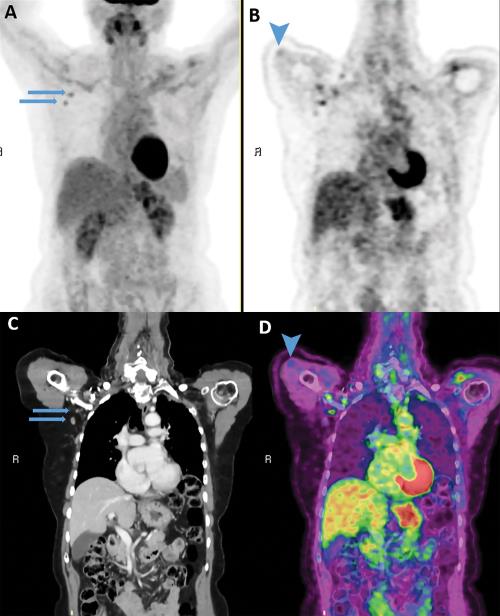

The first runner-up is an article entitled “Imaging of COVID-19 Vaccination at FDG PET/CT” by Michal Eifer and Yael Eshet. This article has been downloaded more than 24,000 times and, having been noticed and disseminated by the lay press, received more attention in online news and social media than 95% of all research publications scored by Altmetric.